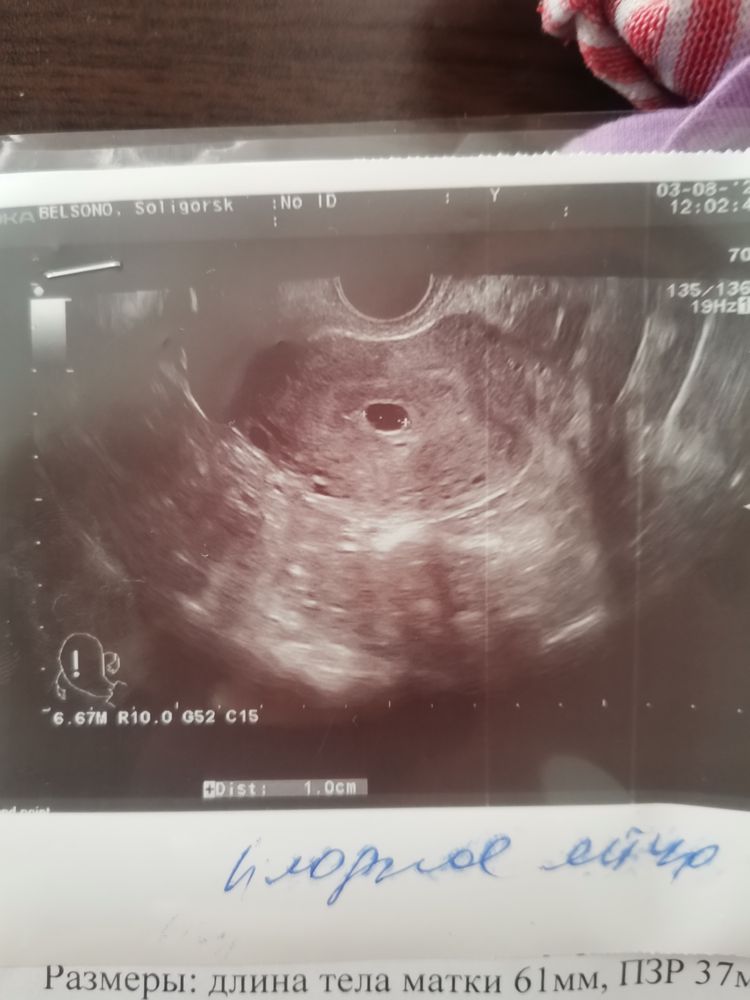

Завтра должно быть по месячным 8 недель, от овуляции приблизительно 5 недель, тесты заполосатились в день Х, еле еле, ровно две недели назад был ПЯ под вопросом в матке, я писала предыдущий пост, есть ли надежда?? Меня просто рвёт на куски, сказали к Гине записываться и возможно чистка, ПЯ 10 мм, эмбриона не видно, под вопросом анэмбриония...

У сожалению, за 2 недели пя совсем чуть-чуть выросло, поэтому прогноз плохой(

Если от овуляции 5 недель прошло,то по УЗИ должно быть 7 недель уже и эмбрион хороший с сб,если точно прошло 5 недель от овуляции (34-35 дпо),то да к сожалению шансов нет,а пя при анэмбрионии может плохо расти и до 20-25 мм не ждут,так как оно врятли до таких размеров вырастет,смотрят срок,ваше пя соответствует 3,5 неделям от зачатия,вот если у вас 3,5 недели от зачатия,то шансы есть,а так увы .. анэмбриония разная бывает,бывает хорошо пя растет и по сроку и даже жм есть,но эмбрион не появляется,тогда есть смысл ждать до размера пя 25 мм,но такое пя при хорошем росте на 35 дпо,а есть когда нет ни жм и пя плохо растет,оно и в 6 недель может 10 мм быть пустое и в 7 недель такого же размера, переделайте УЗИ в другом месте во избежании ошибки и если все так же,то тянуть нет смысла, эмбрион на 30 дпо уже есть 100%,а на 35 дпо крайний срок,но у вас и пя маленькое для срока,видимо хгч тоже плохо рос

mom and baby, я на это надеюсь, я вообще пришла, они сказали, что 10 мм пя, я то и думала, что все хорошо, потому что в 6 недель было под вопросом пя в матке, за день до этого(6 недель) хгч 756, но он удваивался, я и подумала, что может еще рановато для эмбриона, а она мне сходу на чистку, у меня только в 1дз еле еле заполосатился

Мне говорил врач, что в плодном яйце до 15 мм можно не увидеть эмбрион. Переделайте через пару дней

К сожалению на таком сроке, и пя должно быть больше, и эмбрион с сб должен быть. Можно конечно подождать, чудеса случаются …

Екатерина, ну, я просто самые первые полоски увидела в день Х, и за день-два я чувствовала как в матке очень колит, и еще, не знаю, тут в приложении видно или нет, но внутри пя какие то тени, я если честно надеюсь на ошибку, пошла платно, а она посмотрела 2 минуты! 3 раза поводила: матка и яичники, а самое интересное, она мне даже не сказала и не написала ЖТ, хотя на первом узи оно было хорошее в правом яичнике, поэтому я не много успокоилась и в следующую пятницу пойду к другому специалисту, начало тошнить только неделю назад, да и выделения в норме, у меня с первым ребенком в 6 акушерских 4 эмб тоже пя 12 мм, и пустое, и мне тогда ничего не сказали и спокойно гуляла. Меня первач узистка, которая тогда под вопросом поставила ПЯ , она сказала, что похоже, что мало того что овуляция поздняя так еще все зависит от имплантации.. Верю в чудо, что мой малыш просто сел в последний вагон😅😅😅